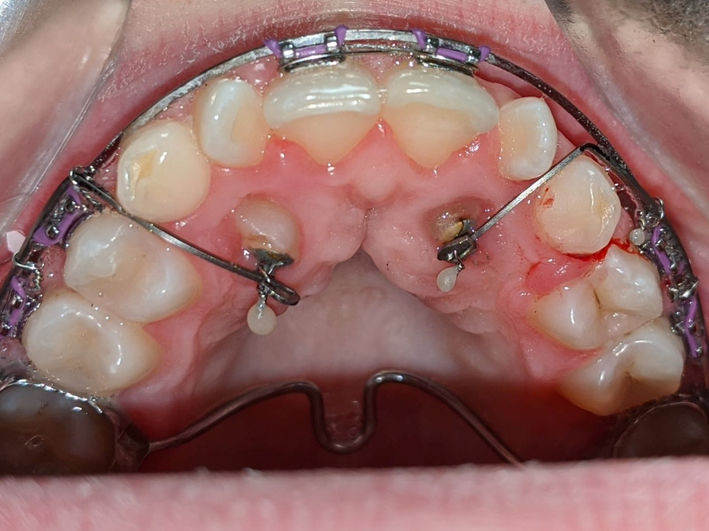

1. Tratamentul caninilor incluși

Caninii incluși sunt acei dinți care nu erup în poziția corectă în cavitatea bucală, rămânând incluși în os sau gingie. Această problemă este destul de frecventă și poate afecta atât estetica zâmbetului, cât și funcția de masticație.

Incidența caninilor incluși variază în funcție de populație și de studiu, dar, în general, se estimează că aproximativ 1-2% din populație este afectată de această problemă. Caninii superiori sunt mai frecvent incluși decât cei inferiori.